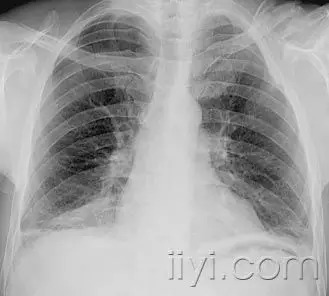

网状影

平片和CT.—在胸片上,网状影是大量细线状影的聚集,简言之,就是形成网状外观,(图)本征象一般代表间质性肺疾病。薄层CT显示网状影的成份更加清晰,可以是小叶间隔、小叶内线的增厚,或者是蜂窝征的囊壁。注意网状影和蜂窝征不是同义词。